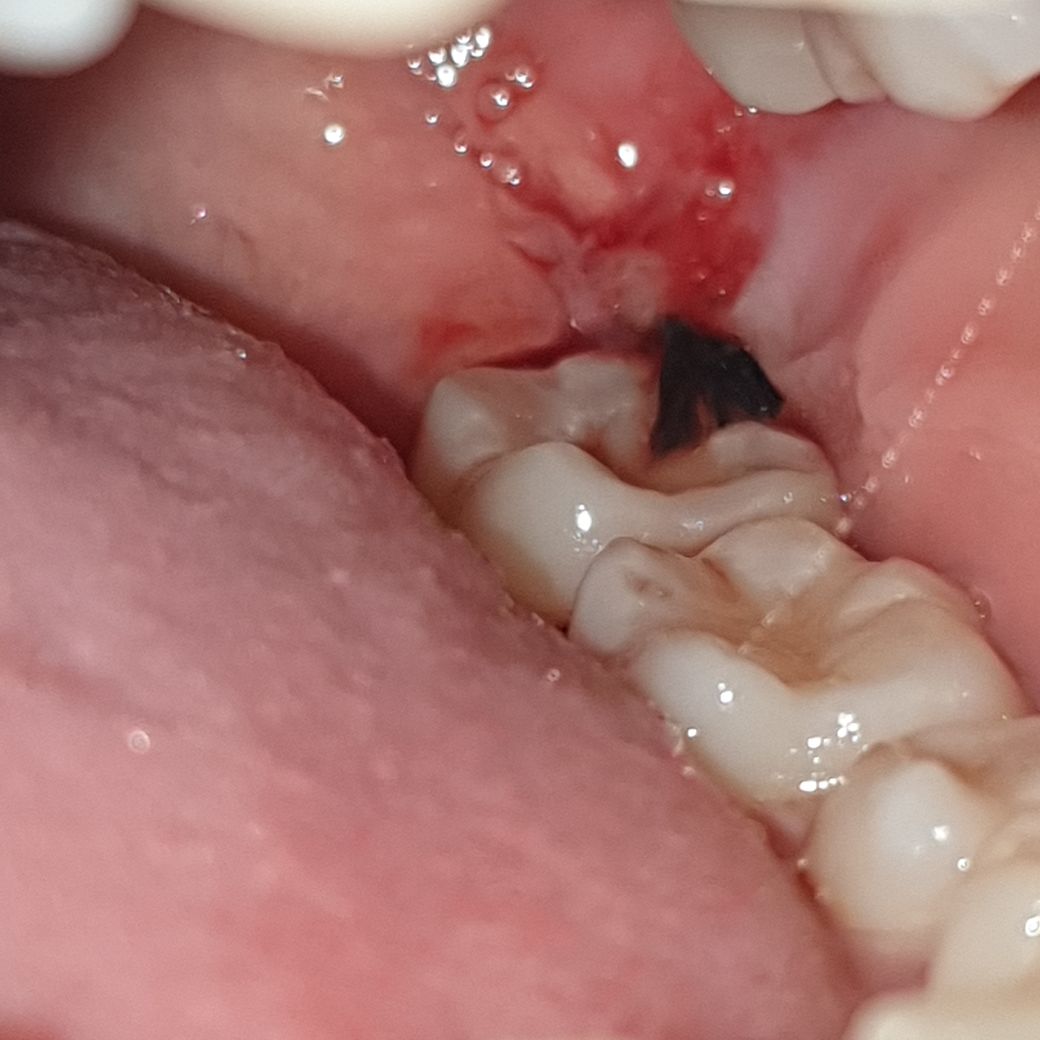

사랑니 발치 3일차인데 너무 부었어요

1, 2일차는 별로 안아팠는데 지금은 턱 부위가 팅팅 부었어요... 상처에서 피도 스며나오는데 잘 아문건가요? 걱정됩니다

ㅠㅠ

이정도는 정상적인 것으로 보입니다. 부어 입이 안벌어져 식사하기도 힘든 케이스도 종종 있습니다. 얼굴이나 볼이 많이 부을 수도 있습니다.

치아를 뽑은 곳 자체는 특별히 문제는 없어보입니다. 붓기는 온찜질 해주시면 금방 가라앉을겁니다.

아직 잇몸이 다 아물지 않아서 그럴수 있습니다. 처방받으신 약을 드시고 시간이 지나면 괜찮아 지실꺼에요.

발치 후 부종은 일주일정도까지도 지속될 수 있습니다 치과에서 처방한 약 잘 복용하시고 푹 쉬시기 바랍니다